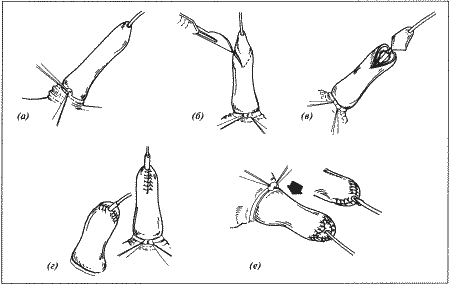

Рассматриваются следующие вопросы: нормальная физиология собак и кошек; болезни репродуктивной системы; бесплодие самок и бесплодие самцов; нормальное функционирование и дисфункция молочных желез; спаривание; искусственное осеменение; протекание беременности и роды; уход за новорожденными щенками и котятами, их наследственные и инфекционные болезни; техника оперативных вмешательств на репродуктивных органах; фармакологический контроль репродукции.

В Руководстве приводится обзор нормальной физиологии и эндокринологии размножения собак и кошек, рассматриваются причины бесплодия самок, функция и дисфункция молочных желез, нарушения, возникающие у небеременных самок, а затем столь же подробно описываются соответствующие проблемы у самцов. Далее обсуждаются вопросы спаривания и искусственного осеменения, а также протекание беременности и родов. Специальный раздел посвящен наблюдению и лечению новорожденных щенков и котят; он включает обзорные данные по наследственным порокам, обсуждение роли инфекционных болезней и мер по их предупреждению. В заключительных главах книги рассматриваются терапевтические и хирургические методы, применяемые для коррекции репродуктивных нарушений.